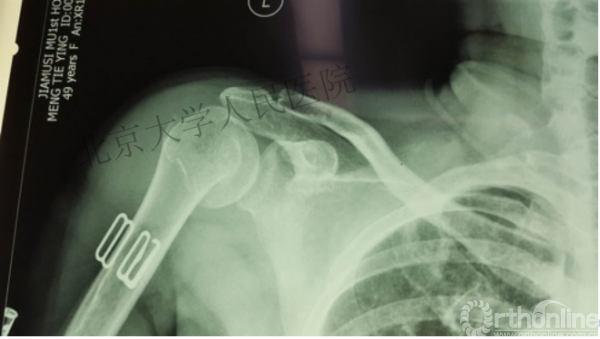

另一个留有遗憾的病例,您的选择?PHN?

临床中的广泛内固定治疗不断地提出思考

三、其实应用肱骨近端髓内钉治疗肱骨近端骨折有时有许多优势。